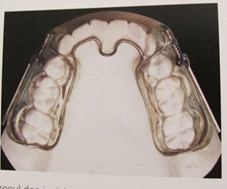

Les appareils d’expansion du maxillaire

Ils permettent d’élargir la mâchoire du haut (le maxillaire) chez un enfant en cours de croissance.

En fonction de l’importance de l’élargissement et de l’âge du patient, on peut utiliser différents outils :

Le quad hélix

Fiche à télécharger : Conseils Quad-Hélix